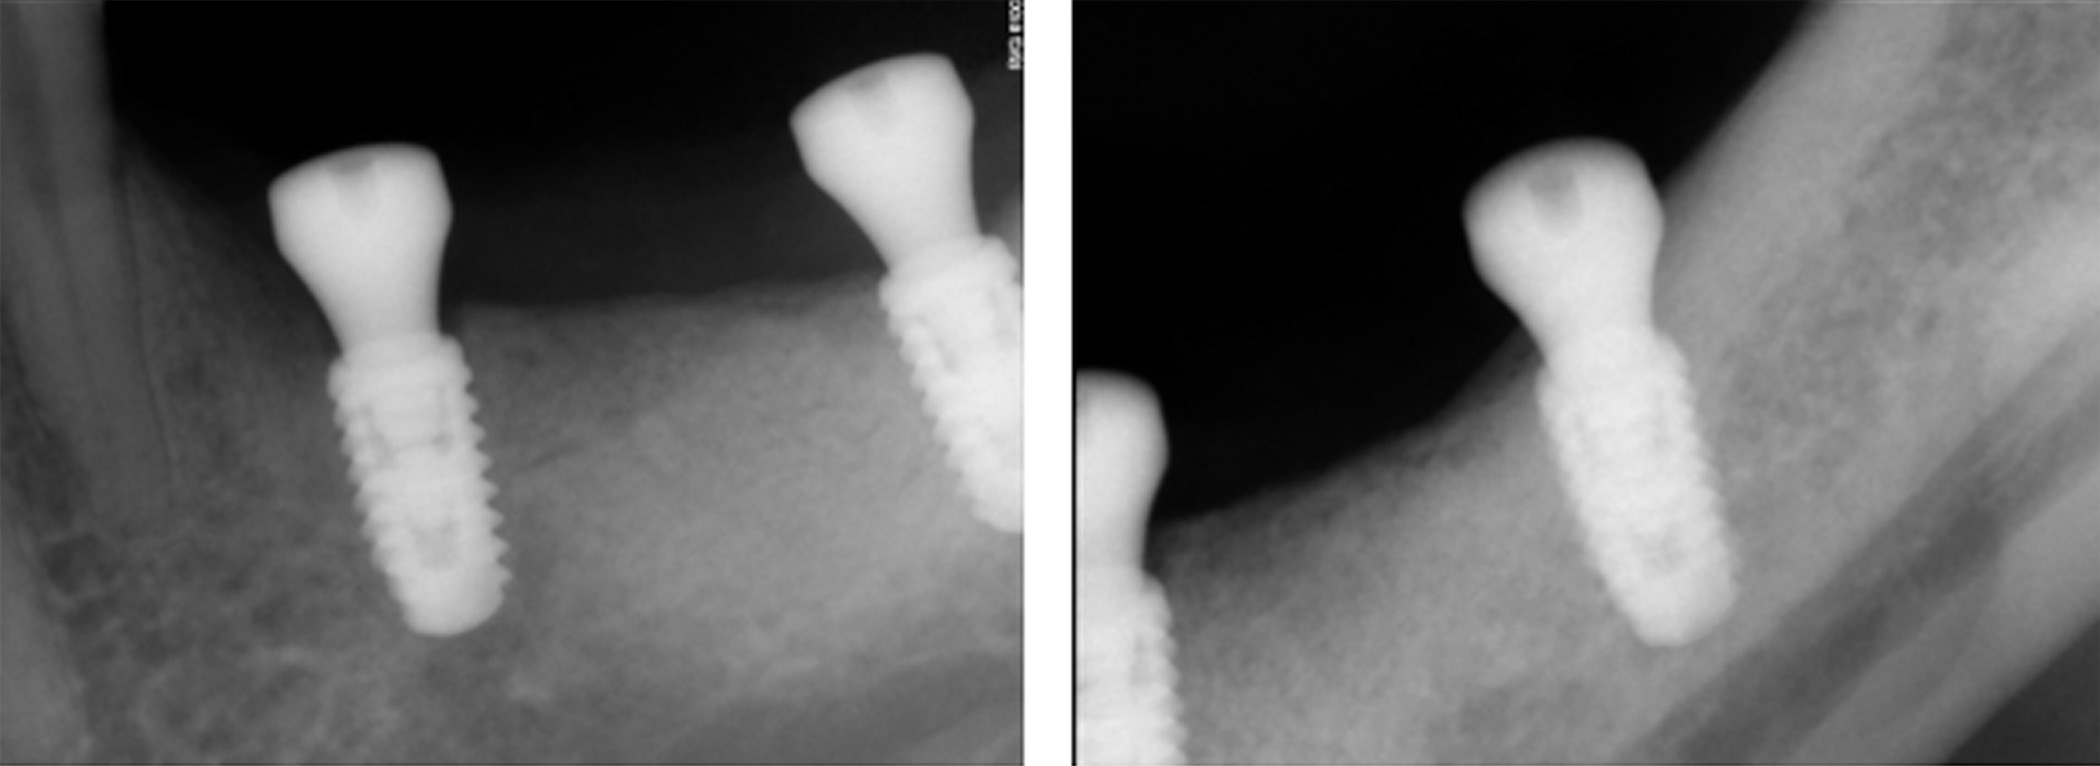

Following removal of the implant bridge and creation of a full-thickness flap, vertical and horizontal bone engagement around the original implants was confirmed with an active infection in progress (Figure 3). Both implants were explanted (Figure 4) with subsequent curettage of the bed and application of a local antibiotic (clindamycin).

Figure 3. After removing the implant bridge and creating a full-thickness flap, vertical and horizontal bone engagement around both implants was confirmed with an active infection in progress

Figure 4. Due to the infection, both implants were explanted with subsequent curettage of the bed and application of a local antibiotic (clindamycin)